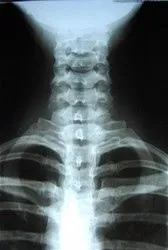

xray.jpg X-rays are one of good sources give the doctor an inside look at what is going on with the bone structure of the entire spine and surrounding skeletal structure. From this x-ray, the doctor can tell your current spine angles as well as any potential further issues including the potential for additional information such as an MRI. Although X-rays are not always necessary for treatment, we refer our patients, who need to be evaluated to rule out any contraindications for chiropractic treatments, to local radiology center for the latest digital X-ray evaluation by medical professionals before Dr. Kim gets the report.